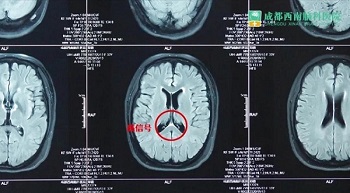

从影像学来看,患者的脑干、大脑还有脊髓都有一些脱髓鞘性疾病症状出现。